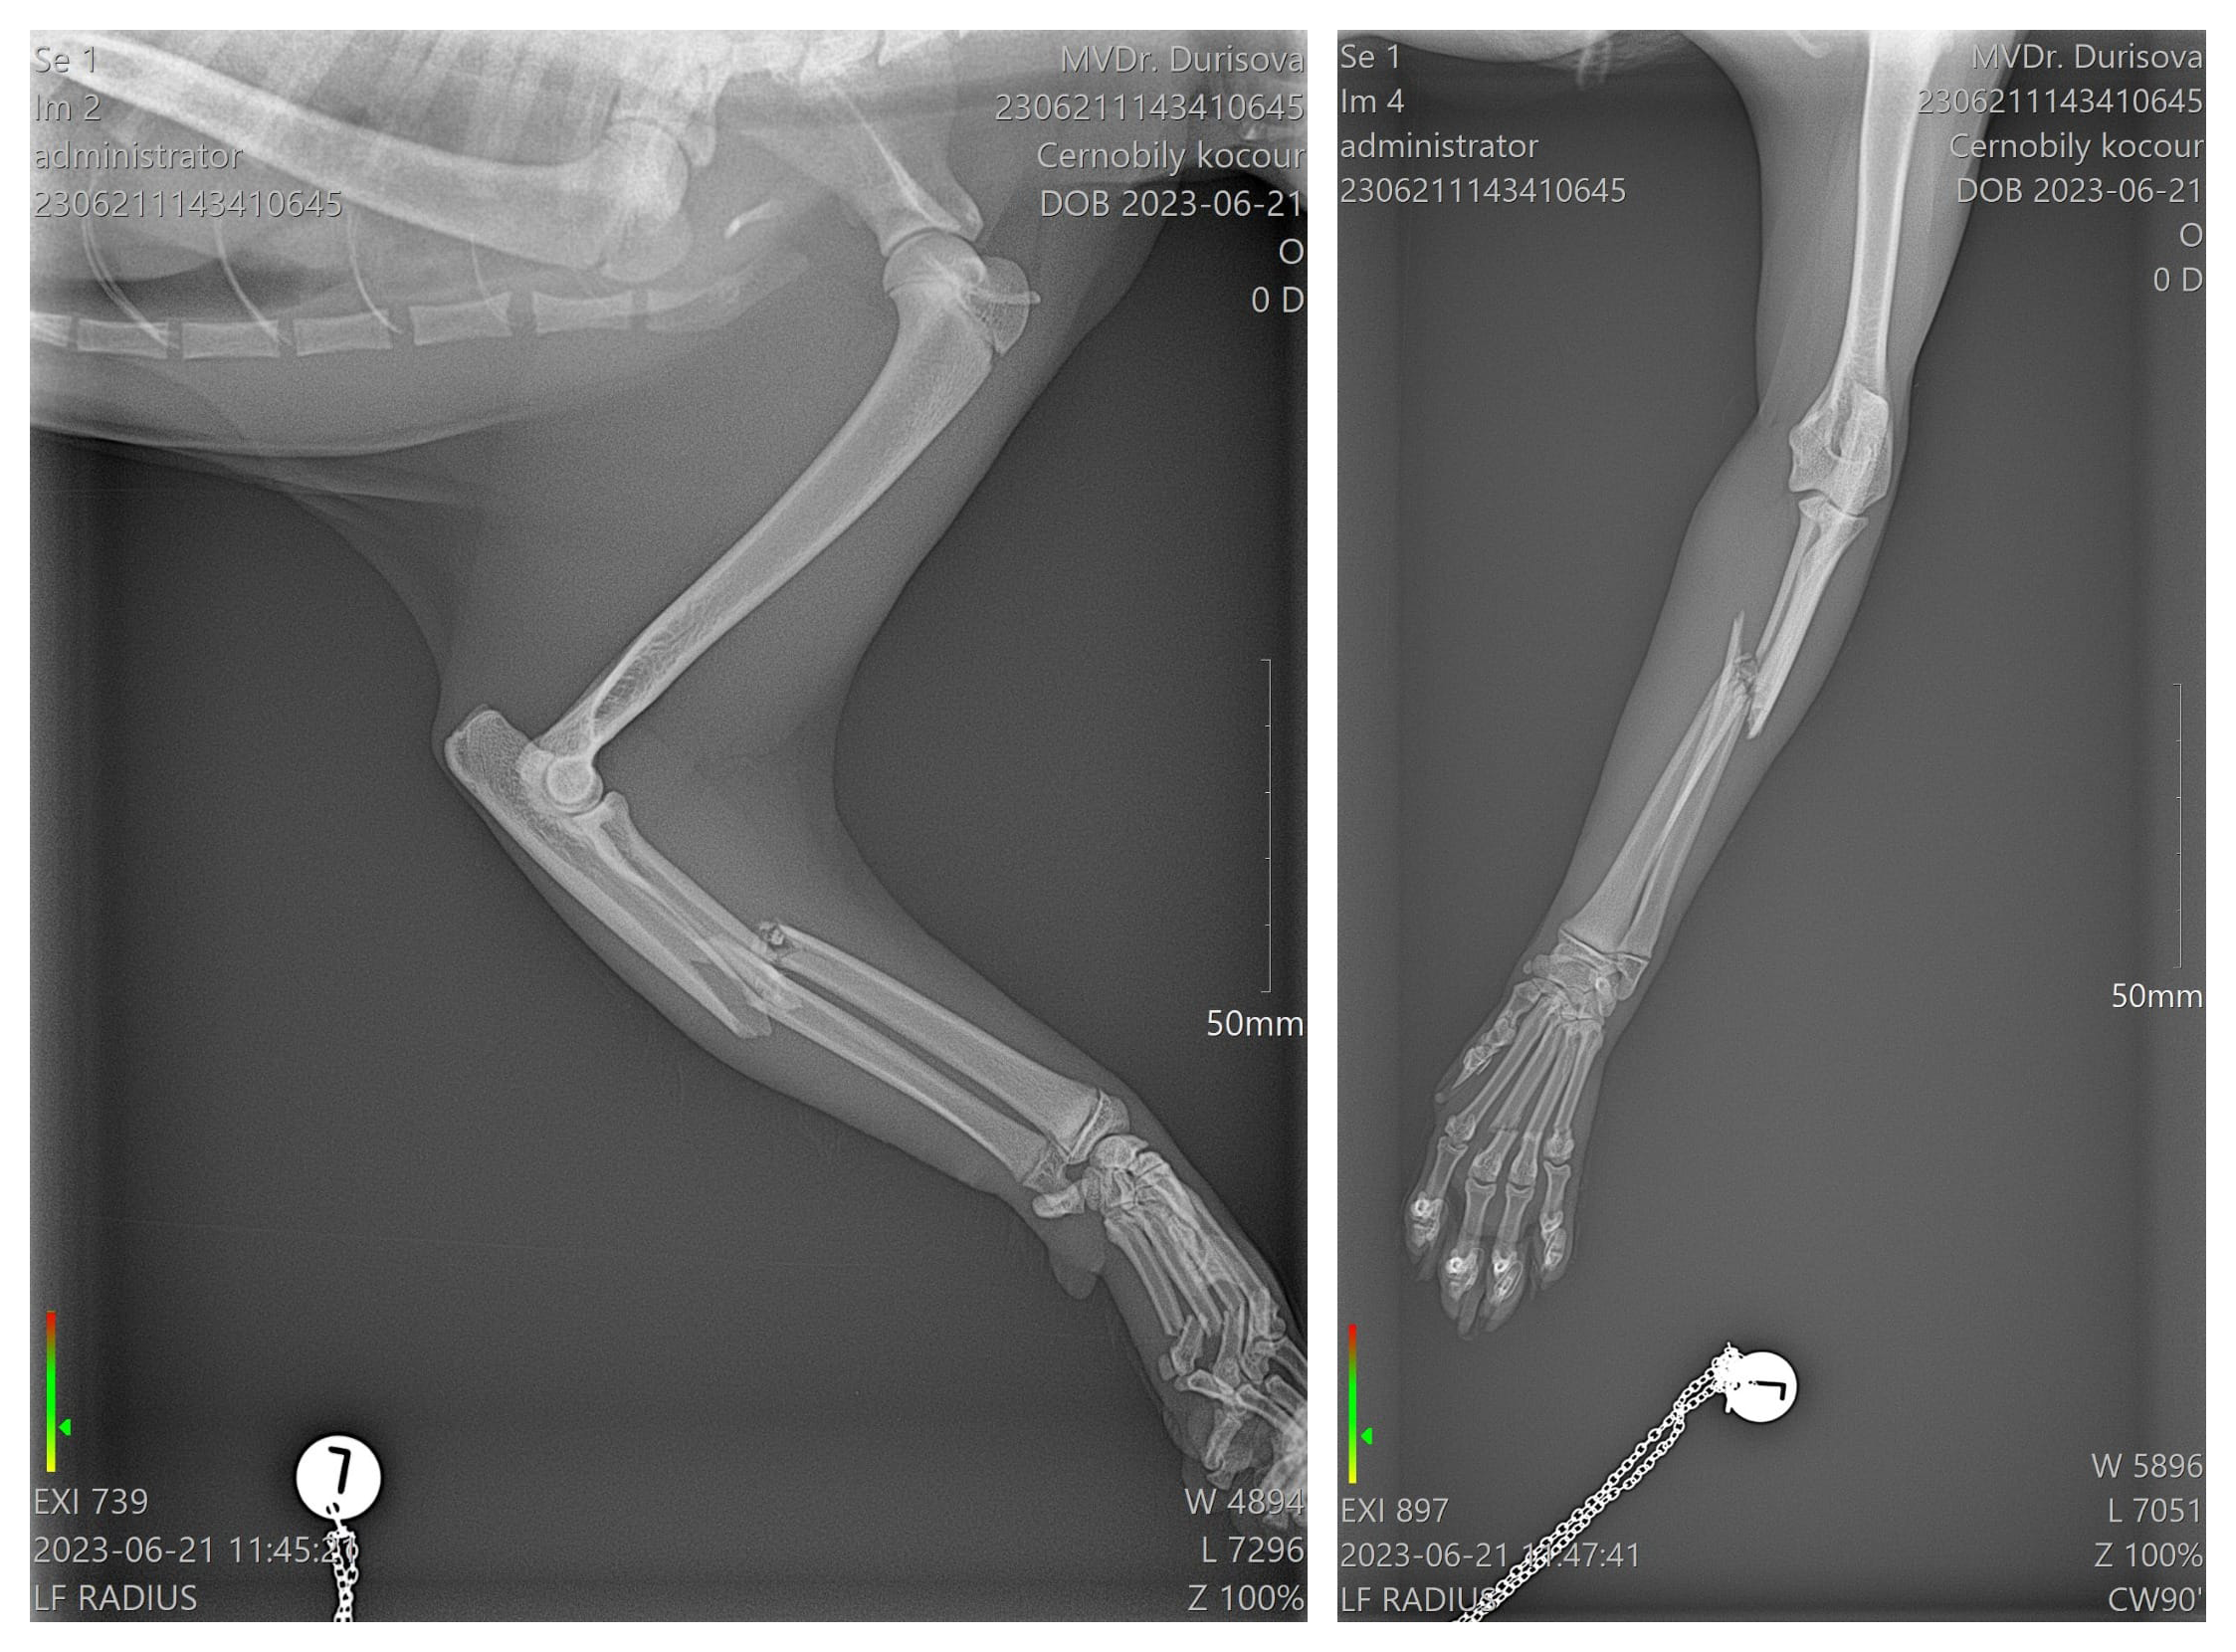

Kocourek vypadl z okna, měl zlámanou tlapku včetně prstíků.